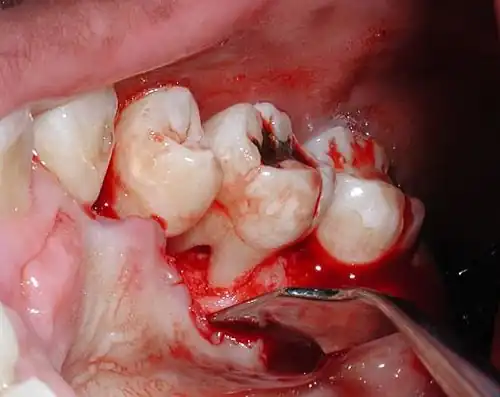

Diagnosis

Nabers probe is used to check for furcation involvement clinically. Recently, cone beam computerised technology (CBCT) has also be used to detect furcation.[5] Periapical and interproximal intraoral radiographs can help diagnosing and locating the furcation.

Only multirooted teeth have furcation. Therefore, upper first premolar, maxillary and mandibular molars may be involved. Upper premolars have one buccal and one palatal root. Maxillary molars have three roots, a mesio-buccal root, disto-buccal root and a palatal root. Mandibular molars have one mesial and one distal root, and so.